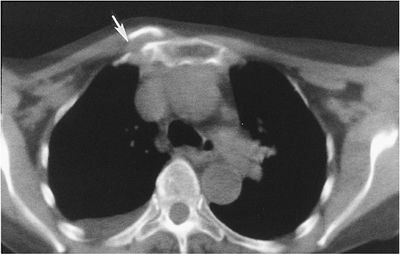

Radiographic evaluation is difficult with

routine views because of bone overlap. CT is the technique of choice to

evaluate the sternoclavicular joint. -

FIGURE 7-8 Axial CT image of an anterior sternoclavicular fracture dislocation (arrow).